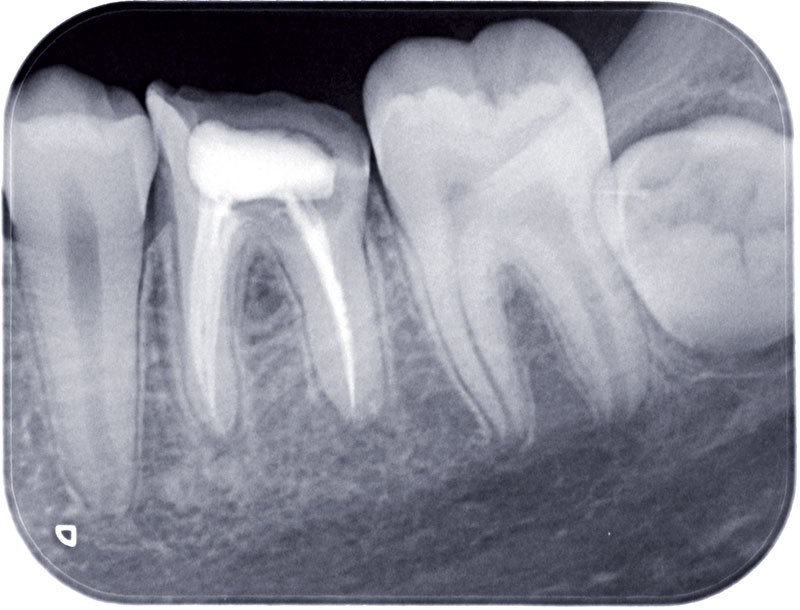

Examen radiographique

Le bilan rétro-alvéolaire révèle une atteinte du plancher radiculaire de 26 et 36 (fig. 10 et 11).